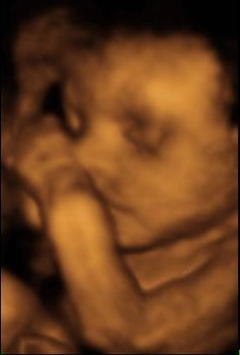

Az újak kedvéért, a régiek már látták:

Ő Léni 19 hetesen, harántban van így jó kis feladat volt ez a kép is:

Lillu 26 hetesen meg így nézett ki: